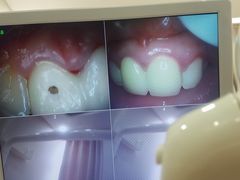

• 藁城德伦口腔医院

• -藁城德伦口腔医院

张博_1789 | 22-03-17

匿名用户 | 22-03-15